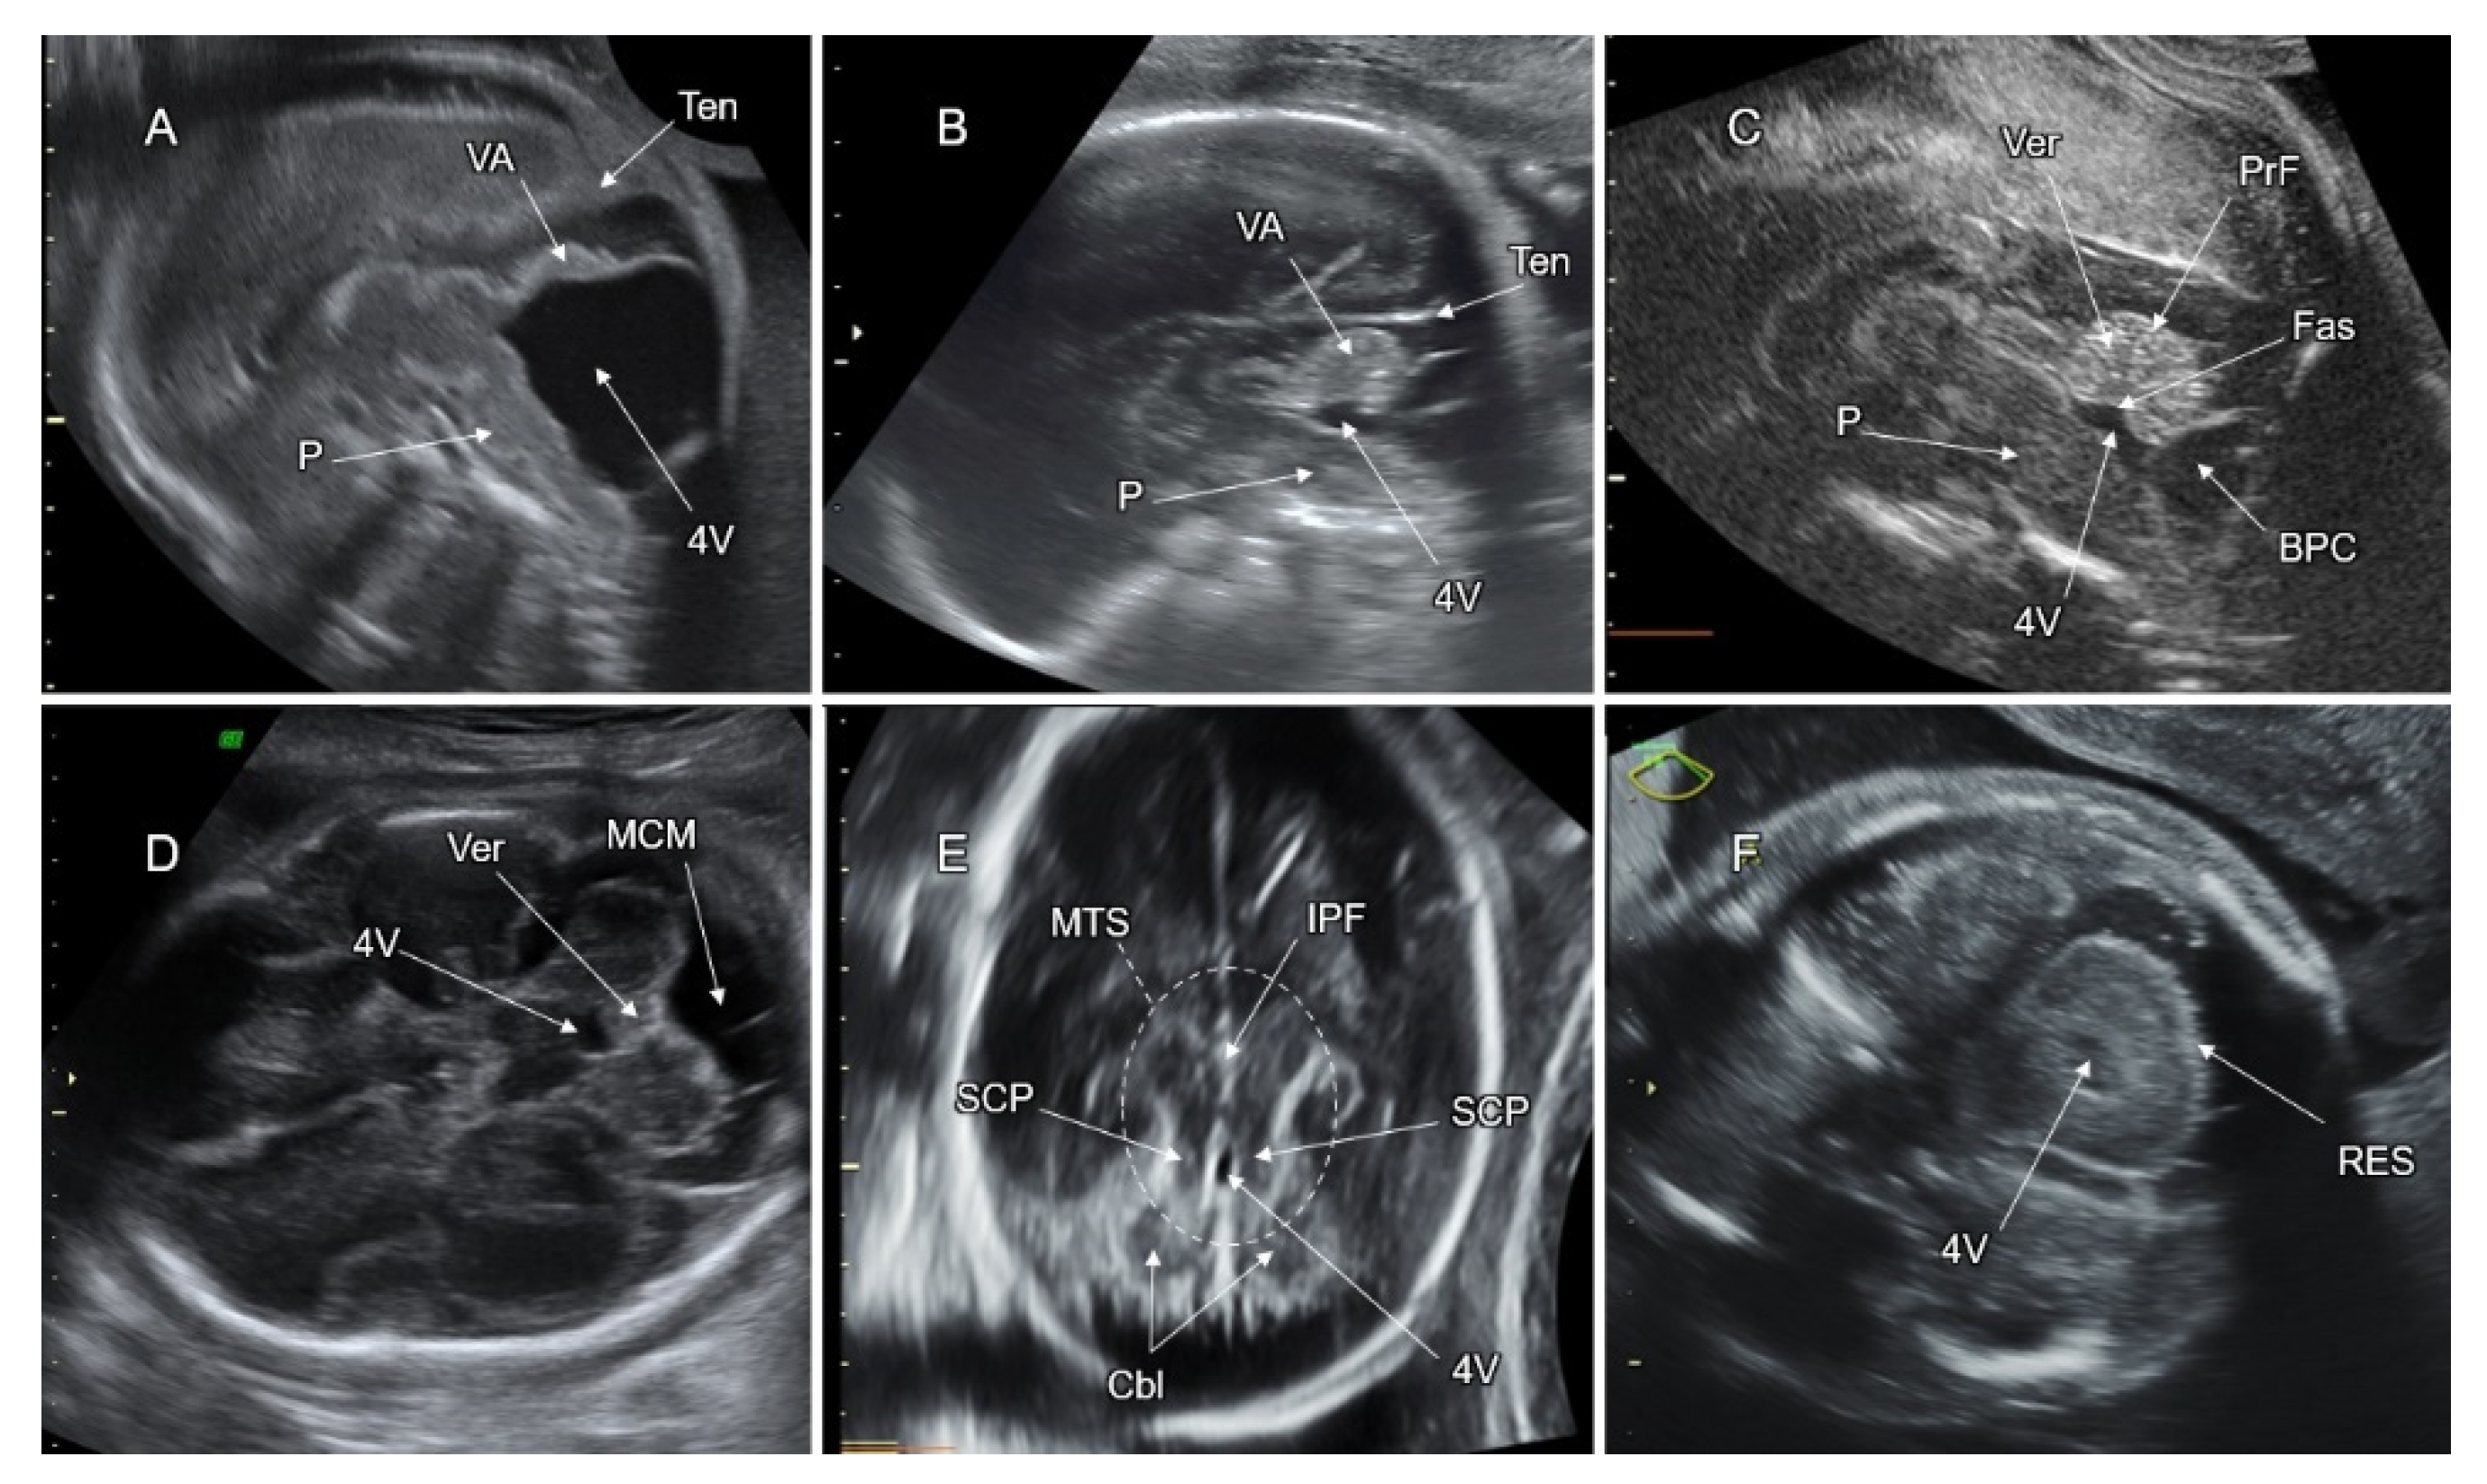

7. Malformations of the Posterior Fossa

7.1. Dandy–Walker Malformation (DWM)

7.2. Vermian Agenesis (VA), Hypoplasia (VH), and Dysgenesis (VD)

7.3. Blake’s Pouch Cyst (BPC)

7.4. Mega Cisterna Magna (MCM)

7.5. Joubert Syndrome (JS) and JS-Related Disorders

7.6. Rhombencephalosynapsis (RES)

7.7. PF Anomalies Associated with Tubulinopathies

7.8. PF Anomalies Associated with Cobblestone Malformation (CM)